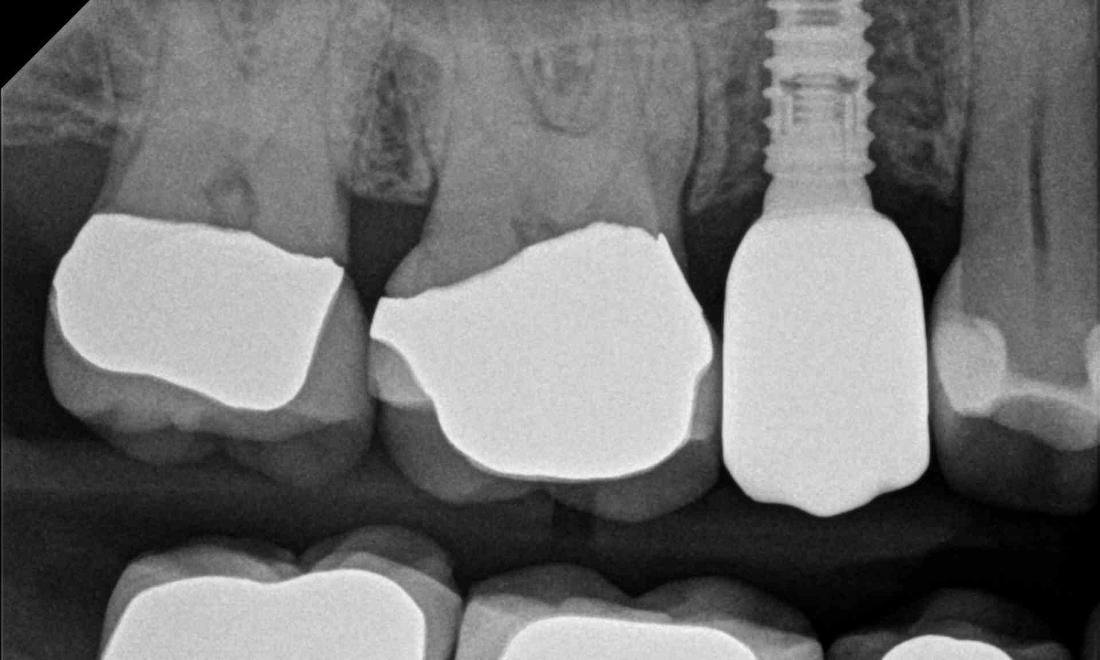

This wonderful patient came to us all the way from Colorado to have a dental implant done. At her first evaluation appointment, an x-ray was taken and Dr. Jordan determined that a minor sinus lift was needed to allow room for a dental implant. The sinus lift and insertion of the dental implant went perfectly! After healing, a tooth colored crown was placed on top of the implant and as you can see, it looks very life-like. She was very pleased.